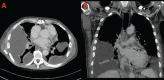

Primary pericardial malignant mesothelioma (PMPM) is extremely rare with an incidence less than 0.0022%. It comprises 0.7% of all mesothelioma cases. To date, approximately 350 cases of pericardial mesothelioma have been reported in the literature. Its typical presentation is insidious, with nonspecific signs and symptoms, and usually results in constrictive pericarditis, cardiac tamponade and congestive heart failure either by a serous effusion or by direct tumorous constriction of the heart. With the exception of several case reports, the outcome is uniformly fatal, and patients typically die within six months of diagnosis. Here we report a 72-year-old Cauca -sian male with persistent pericardial and pleural effusion. He was diagnosed with PMPM after pericardectomy. He had only one cycle of chemotherapy with cisplatin and pemetrexed. He developed acute kidney injury as result of chemotherapy. He died 1 month after diagnosis and 6 months after the first symptoms.